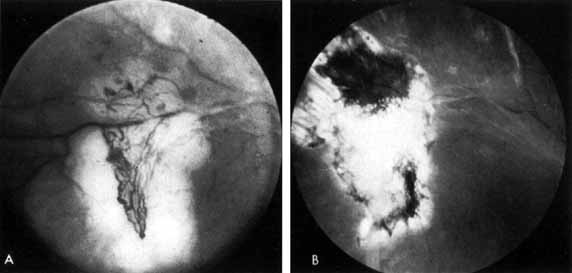

Although microaneurysms are the first ophthalmoscopically detectable change in diabetic retinopathy, the earliest abnormalities seen histopathologically are thickening of the capillary basement membrane1,2 and pericyte dropout.3,4 Pericytes are mesothelial cells that surround and support the retinal capillary endothelial cells. Normally there is one pericyte per endothelial cell. In people with diabetes, however, the pericytes die off and are decreased in number (Fig. 1). Their absence weakens the capillaries and permits thin-walled dilatations, called microaneurysms, to develop. Later, endothelial cells proliferate and lay down layers of basement membrane material. Fibrin may accumulate within the microaneurysm along with erythrocytes, and the lumen of the microaneurysm may become occluded (Fig. 2). Initially, most microaneurysms are on the venous side of the capillaries, but later they are seen on the arterial side as well. Clinically, they appear as small red dots (Fig. 3). Despite the multiple layers of basement membrane, microaneurysms are permeable to water and large molecules, allowing the transudation of fluid and lipid into the retina.

Fig. 1 A. Trypsin digest preparation of early background retinopathy. Normal retinal capillaries, with one pericyte (closed arrows) per endothelial cell (open arrows). B. Retinal capillary of a patient with diabetes with necrotic pericytes (arrows). (Courtesy of Dr. Myron Yanoff)